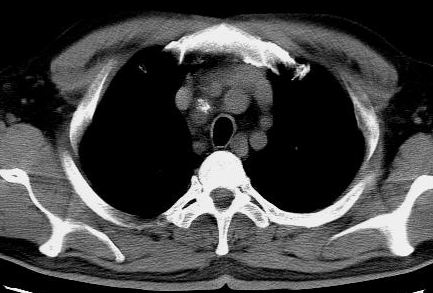

标题: CT15869:男性,71岁,因咳嗽而就诊,请讨论右上肺病变性质 [打印本页]

标题: CT15869:男性,71岁,因咳嗽而就诊,请讨论右上肺病变性质

患者,男性,71岁,因咳嗽而就诊,

典型的右肺中心性肺癌并纵隔淋巴结转移

考虑右肺中心性肺癌并右肺门及纵隔淋巴结转移。

1,右肺中心型ca,气管隆突旁淋巴结转移。